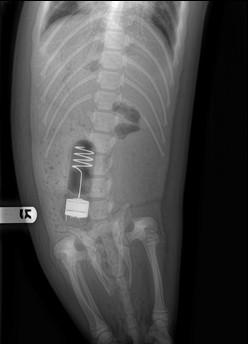

Science SpotlightSurvival and Depredation in Harbor SealsHarbor seal (Phoca vitalina) abundance in the Aleutian Island chain of Alaska has experienced a greater than 60% decline over the last twenty years. Currently, the factors that may be influencing harbor seal survival, pup production and population trends remain poorly understood. Scientist are considering changes in prey availability, bycatch in fishing gear, entanglement in marine debris, disturbance by fishing and tourism industry, pollution, predation, and general environmental and climate change as potential causes to the declining population trends. While transient killer whales are a widely accepted predator of harbor seals, less known possible predators include white sharks, salmon sharks and Pacific sleeper sharks. Increasing our understanding of harbor seal survival, including dates, locations, and causes of mortality, as well as female recruitment and pup production, is essential in understanding population trajectories. The collection of such fine scale life-long data requires the use of specialized tags.